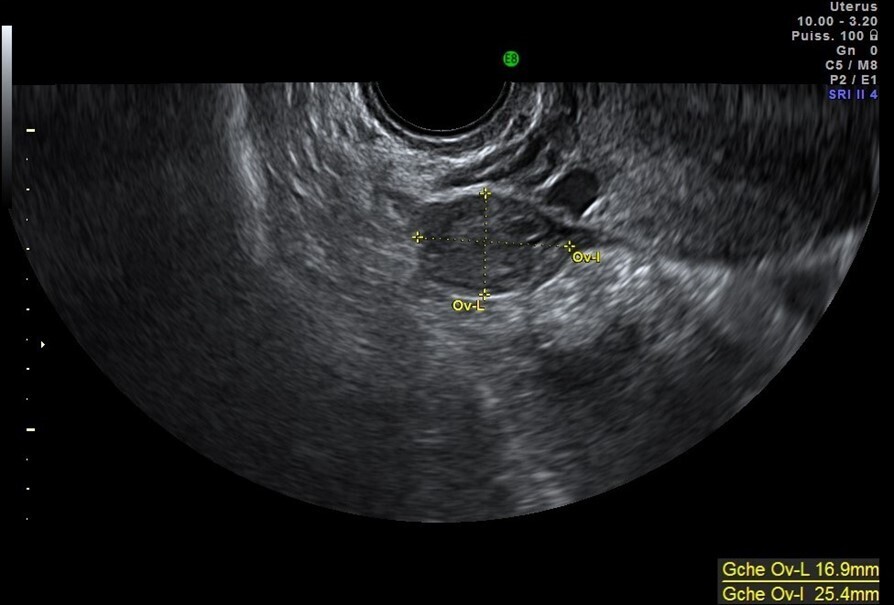

Vous faites une échographie pelvienne qui retrouve un utérus antéversé avec un endomètre épaissi de 5 mm, des ovaires droit et gauche sans anomalie. Il n’y a pas d’épanchement dans le cul-de-sac de Douglas.